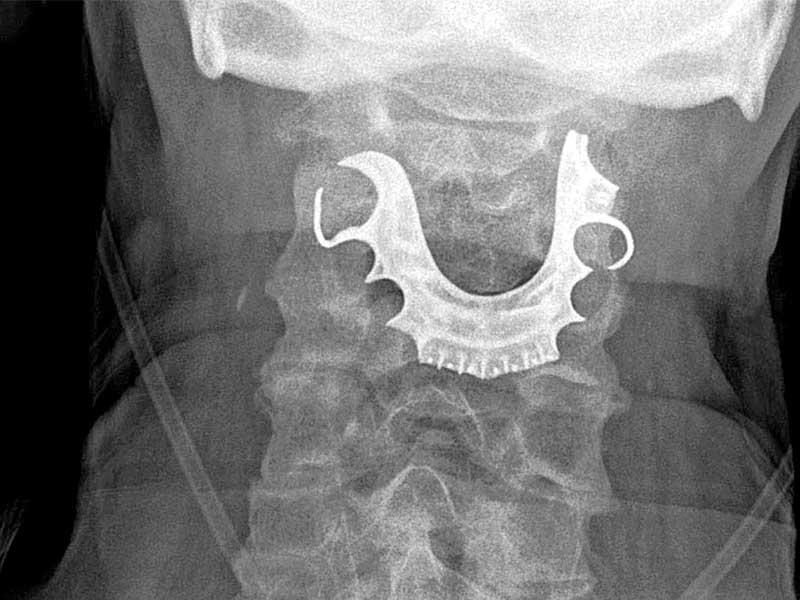

وعندما أخبره الأطباء بما اكتشفوه، تذكَّر الرجل أنه فقد طقم أسنان مؤلفاً من لوحة معدنية و3 أسنان أمامية، خلال العملية الأولى. وتبيَّن لاحقاً أن الجسم هو طقم أسنانه فعلاً، فخضع لجراحة عاجلة لإزالته، وغادر المستشفى بعد ستة أيام.